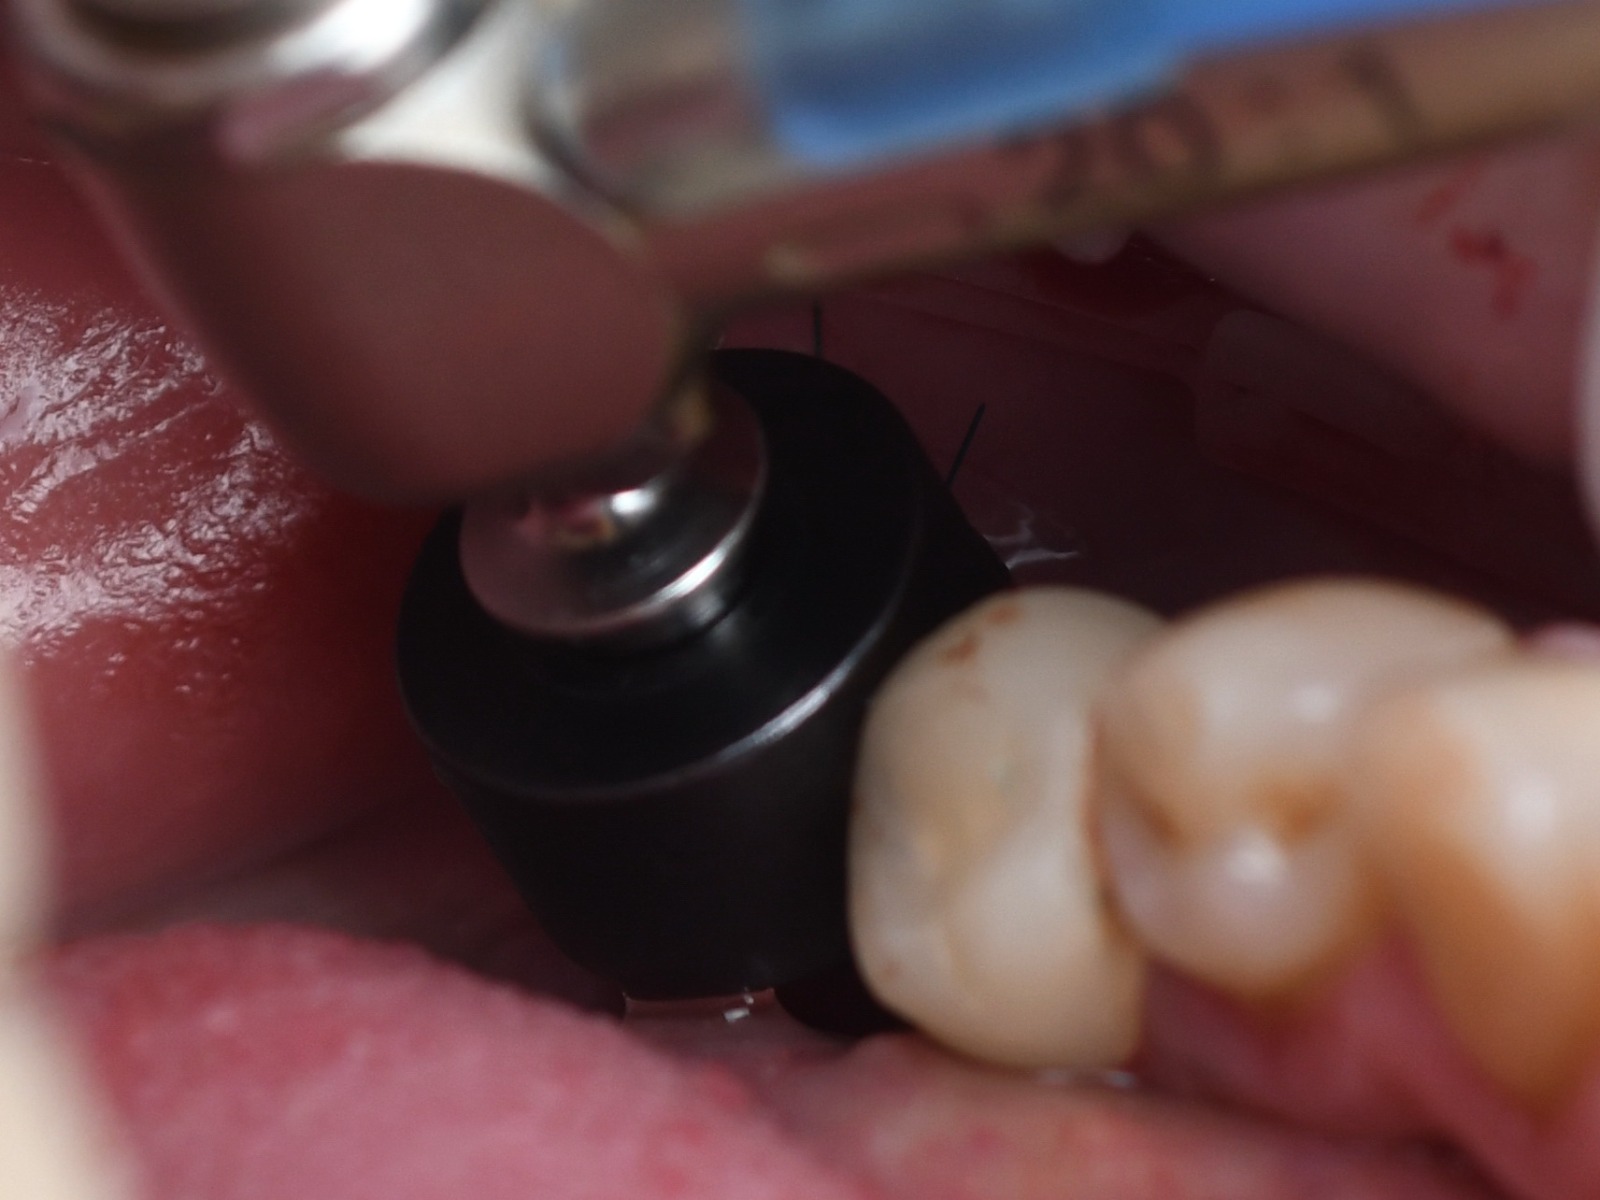

Thin ridge section will be widened using Densah® Burs

Stopper and Guide Positioner Pin 10.5 from IPO kit were used to plan the space for the further restoration

Green Line Premium 4.2x11mm implant was chosen

The view on the placed implant

Using Unilite Flowable Nano-composite and TTA Temporary titanium abutment, custom healing cap was prepared